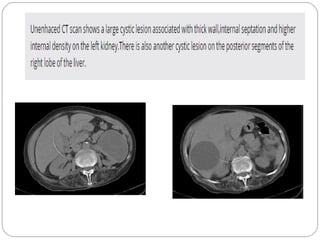

Unenhanced CT

 Cysts complicated by prior infection or haemorrhage

 Thick wall

 Irregularity at the base of the cyst

 Septations

 Calcifications

 High attenuation values

 Contrast enhancement